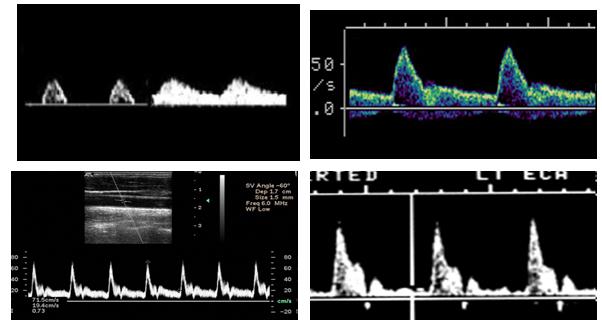

Where is the waveform?

ICA

CCA

ECA

vertebral

subclavian